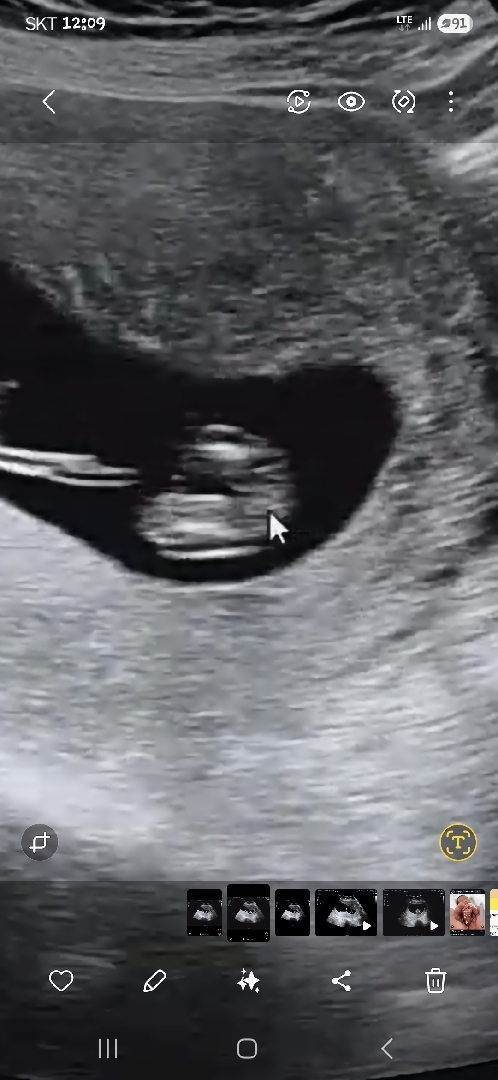

저도 성별봐주세요~아들셋맘ㅠㅠ

아들셋에막둥이예요 너무궁금해요ㅜㅜ

엉덩이 다리사이 인가여? 다른사진도 보여주세요 !